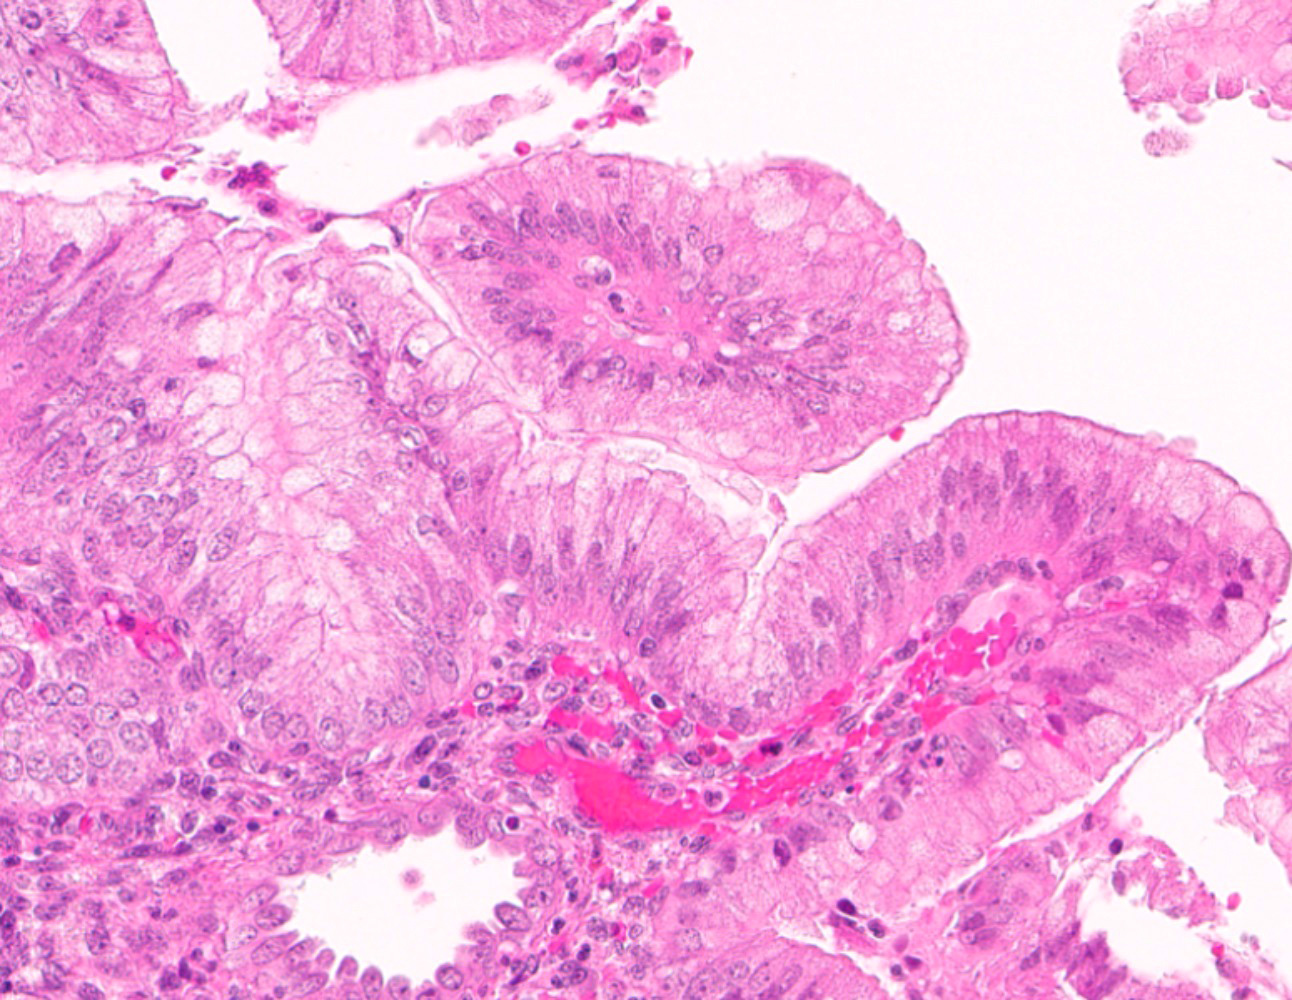

Microscopic (histologic) images

Contributed by Jessica L. Bentz, M.D.

- Papillary metaplasia (Am J Surg Pathol 2013;37:167):

- Subtypes:

- Papillary syncytial: pseudostratified eosinophilic cells with indistinct cell borders and loss of nuclear polarity (Int J Gynecol Pathol 2012;31:206)

- Sometimes termed as pseudopapillary due to the absence of fibrovascular cores

- Generally located on the surface

- Associated with stromal breakdown

- Papillary proliferations: true papillae with fibrovascular cores (Am J Surg Pathol 2001;25:1347)

- Simple / localized: short, nonbranching

- Complex / diffuse: numerous branching with papillae and micropapillae

- Analogous to endometrial intraepithelial neoplasia / atypical hyperplasia